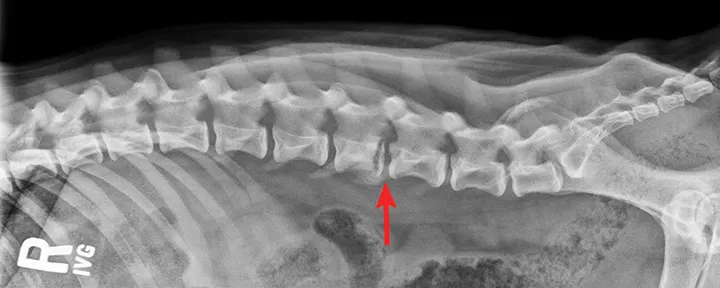

An MRI was performed and revealed indistinct periosteum with irregular physeal bone and no obvious sign of trauma at the level of L5 (Figure 2). The caudal endplate of L4 and the associated epidural space became strongly enhanced after administration of gadolinium contrast.

Sagittal T1+ contrast MRI revealing indistinct periosteum with irregular physeal bone at the level of L5, with strong enhancement of the L4 caudal endplate and associated epidural space (arrow)